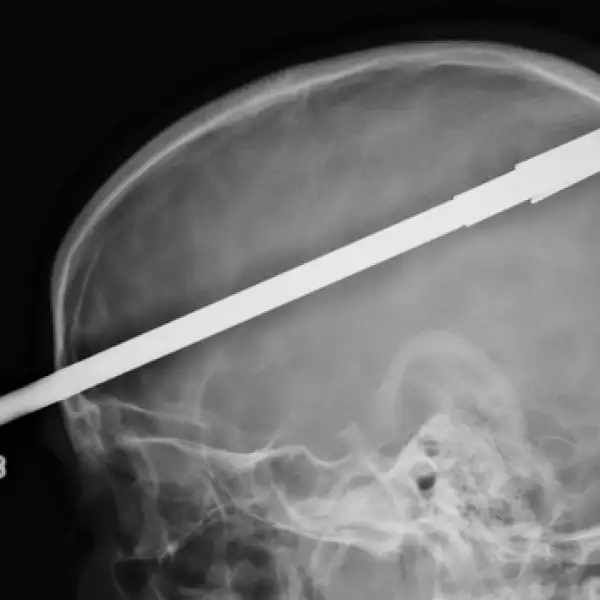

Un joven sobrevive luego de que un arpón de pesca atravesara su cráneo

Yasser López, logró sobrevivir después de que su amigo le disparara accidentalmente un arpón en un lago de Florida